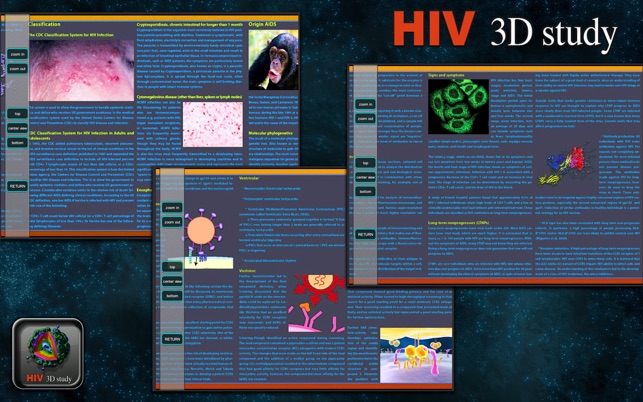

This is an application that shows the HIV reference (encyclopedic) study and 3D digital cell with pins to show each part of HIV cell structure.

Also a slide encyclopedia about HIV reference, forms of infection, advances in medicine, development, progress of the disease, different categories and much more about this disease.

Even ways to prevent it.

Study includes topics such as:

- HIV reference part 1.

- HIV reference part 2.

- Drogs develop

- Category effect

- Investigation

- Epidemiology